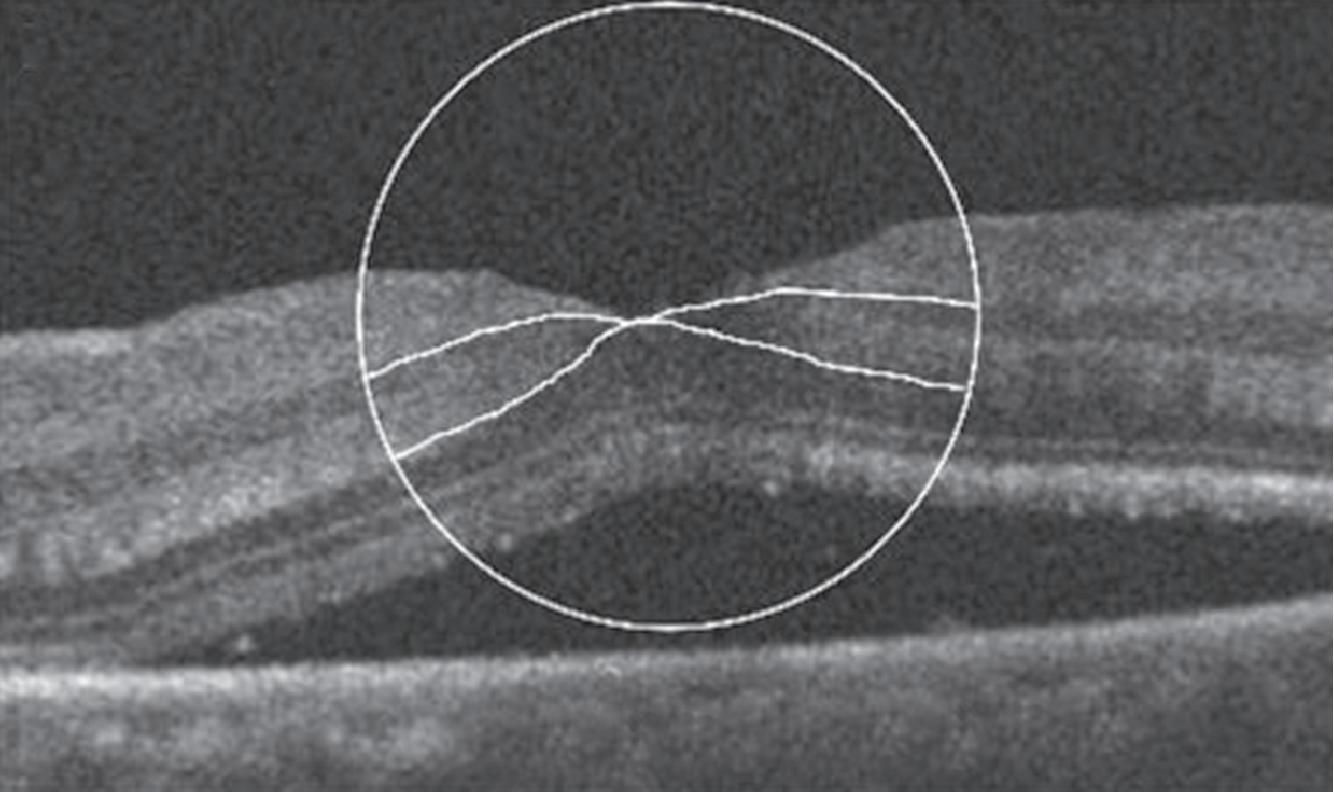

Um exemplo da capacidade da OCT para prever a acuidade visual pós-operatória em olhos com descolamento de retina regmatogênico (RRD) sem mácula está na Figura 1-27.20 Outras áreas da medicina se beneficiam igualmente da técnica da tomografia de coerências ótica . Para citar algumas: dermatologia no diagnóstico de lesões da pele como carcinomas etc. Na cardiologia se usa para obter imagens de alta resolução das artérias coronárias. O método de OCT por endoscopia foi introduzido em 1997 pelo pesquisador James Fujimoto no MIT e outros colaboradores. Finalmente, na indústria de semicondutores na medição não destrutiva das camadas finas dos seus dispositivos. O campo das aplicações do uso da OCT é cada vez mais amplo e se pode afirmar que novos e melhores equipamentos estão por vir.

1-27. Imagens pré-operatórias de tomografia de coerência óptica (oCT). Um círculo com um diâmetro de 2 mm foi posicionado manualmente no centro da superfície foveal da mácula destacada na imagem de oCT. a área macular dentro do círculo foi dividida em três seções: camada interna (superior direita: camada de fibras nervosas e camada de células ganglionares), camada intermediária (inferior direita: camada plexiforme interna e camada nuclear interna) e camada externa (inferior esquerda: camada plexiforme externa e camada nuclear externa). (reproduzida com permissão de https://www.hindawi.com/copyright/.)20